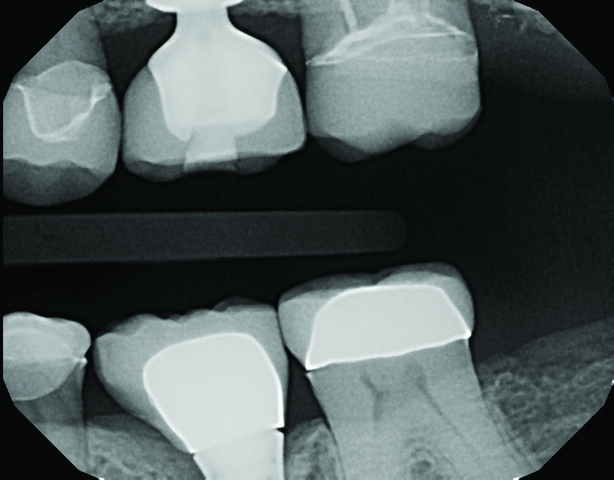

A 64-year-old woman presented with a chief complaint of food packing to the front of her implant. Clinical and radiographic examination revealed an existing Straumann Soft Tissue Level (RN) implant (Straumann, straumann.us) for tooth No. 19, restored with a prefabricated solid abutment and a PFM crown. The mesial marginal ridge of the PFM No. 19 was fractured, leaving an open proximal space between No. 19 and No. 20 (Figure 1).

Fig 1. The mesial marginal ridge of the PFM tooth No. 19 is fractured, leaving an open proximal space between teeth Nos. 19 and 20.

Figure 1